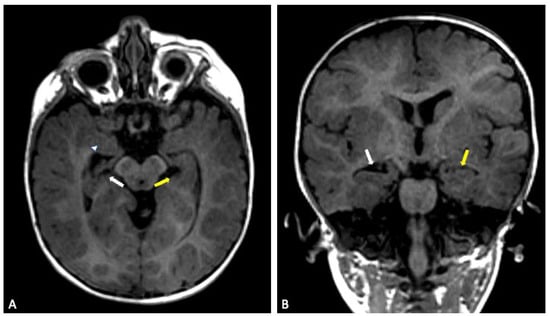

Our sibling series exemplifies this variability (Figure 5 and Figure 6). The eldest child presented with early hypotonia, delayed motor and cognitive development and increasing macrocephaly during infancy. Brain MRI revealed enlargement of the ventricular system, thinning of the posterior corpus callosum and clear hippocampal atrophy. Additional findings included subtle cerebellar hemisphere hypoplasia and a cerebrovascular variant involving asymmetric fusion of the caudal basilar artery together with ectasia of a posterior thalamic perforating branch. These structural abnormalities corresponded to persistent executive and attentional difficulties that remained evident at school age.

Figure 5. Sibling 1. Brain MRI; sagittal (A) and axial (B) T2-weighted turbo spin echo (TSE) images showing slight enlargement of the ventricular system. In (A), a prominent flow void (red arrows) is seen within the third ventricle, the cerebral aqueduct, the fourth ventricle and the prepontine cistern, expressing turbulent CSF flow, in keeping with no evident obstruction of CSF flow through ventricles and cisterns. Focal thinning of the posterior corpus callosum at the body-splenium junction can also be noted (white arrow in (A)).